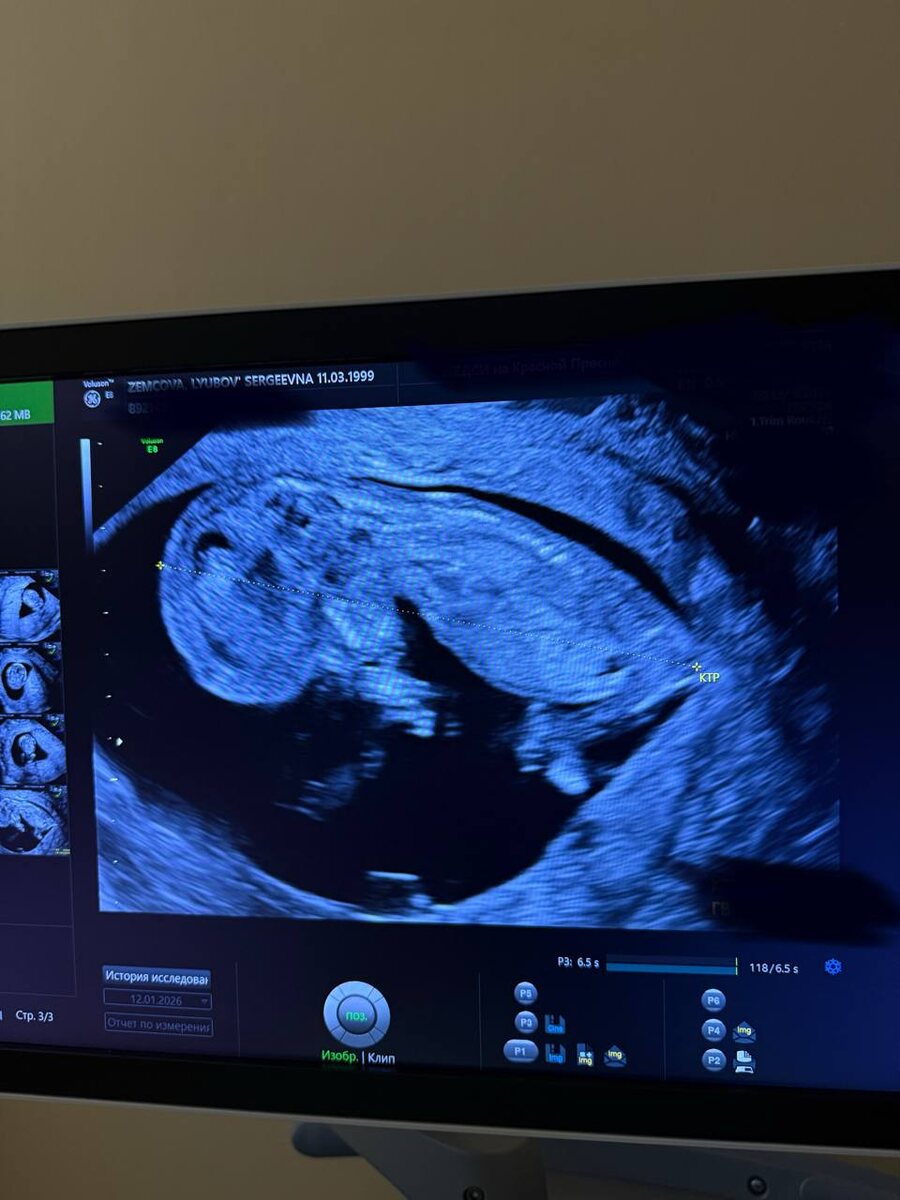

такой большой уже человек🥹 внутри меня!! в животе… вроде не первый раз, а шок такой же